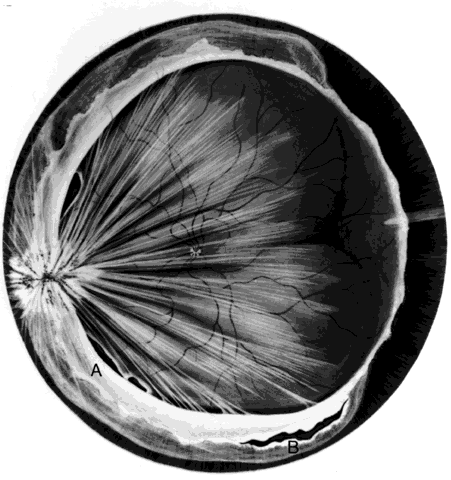

Retinal lacerations are produced whenever the eye is penetrated posterior to the ora serrata. They occur at the site of scleral perforation and at the point of impact or exit of foreign bodies. Lacerations caused retinal detachments in 12 (20%) of 60 eyes reported by Cox and Freeman.20 In 9 eyes, the lacerations occurred at foreign-body impact sites (Fig. 5). Faulty technique during magnet extraction caused iatrogenic retinal lacerations in 2 eyes. Only 1 eye developed a retinal detachment from a laceration at the point of scleral perforation because of the previously described self-sealing characteristics of these breaks.

Fig. 5. Retinal laceration from impact of foreign body. Retinal detachment due to ocular penetration. (Cox MS, Freeman HM: Retinal detachment due to ocular penetration. I. Clinical characteristics and surgical results. Arch Ophthalmol 96:1357, 1978. Copyright 1978, American Medical Association.)

Intraretinal nonmagnetic foreign bodies and embedded magnetic IOFBs unsuitable for posterior transscleral magnet extraction because of their large size, posterior location, or the presence of opaque media are removed by vitreous microsurgery. Intraretinal magnetic IOFBs are not removed by magnet through the pars plana because their passage through intervening retina can produce large lacerations and detachments (Fig. 11).20 Approached and exposed in the same manner described above, they are gently dislodged, grasped with foreign-body forceps, and removed. A lighted pick can be used to manipulate the IOFB into a position or orientation favorable for a secure grip by diamond-coated forceps. Alternatively, magnetic intraretinal foreign bodies may be elevated to the midvitreous by a rare earth magnet, after which they are removed by forceps (Fig. 12) to avoid being dislodged in the vitreous base, as often occurs when extraction by the magnet itself is attempted. Intraretinal foreign bodies of 1 to 2 weeks' duration may become encapsulated (Fig. 13A), in which case the capsule is incised by a myringotomy knife or sharp needle before it can be grasped by forceps or dislodged by the rare earth magnet (see Fig. 13B).

Fig. 11. Laceration by foreign body dragged through retina during magnet extraction. Initial location of foreign body (A). Extraction site (B). Retinal laceration (C). (Cox MS, Freeman HM: Retinal detachment due to ocular penetration. I. Clinical characteristics and surgical results. Arch Ophthalmol 96:1358: 1978. Copyright 1978, American Medical Association.)